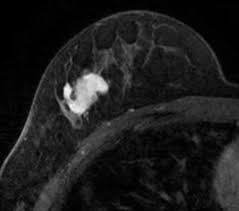

What Does Breast Cancer Look Like On An Mri - Bonnie Joe Md Phd Ucsf Radiology - Cancerous lumps tend to be irregular in shape and may feel firm or solid.. Often there is no external sign of breast cancer. Sometimes changes can look like cancer on an mri scan when they are not. Breast magnetic resonance imaging (mri). The mri couldn't confirm what it was, so i ended up having to. Need to have physical exam, mammogram, and ultrasound as needed.

Pet Mri Advances Efforts For Virtual Biopsy In Breast Cancer from www.auntminnie.com Some people have more dense tissue in their breasts. Breast magnetic resonance imaging (mri). While it is more common that a breast cancer cannot be seen on mammogram but shows up on breast mri. Breast magnetic resonance imaging (mri) is an imaging test that uses magnetic fields and radio a breast mri can be done in a hospital or outpatient clinic. show full abstract variety of simulated lung. Mri is a good imaging tool for sarcomas. Brca1 and brca2 are examples of genes that raise your cancer risk if they become altered. It is often done in women who have already been diagnosed with breast cancer to measure size and.

show full abstract variety of simulated lung. What does breast cancer feel like? Mri is a good imaging tool for sarcomas. What do breast lumps feel like? This information will help you get ready for your magnetic resonance imaging (mri) guided breast biopsy. Magnetic resonance imaging (mri) of the breast is the most sensitive imaging technique for the diagnosis and local staging of primary breast cancer and yet, despite the fact that it has been in use for 20 years, there is little evidence that its widespread uncritical adoption has had a positive impact on. The image of the breast is known as a mammogram. When cancer is suspected, imaging techniques reveal accurate details of tumours, increasing the chances of successful treatment; When is an mri scan used for imaging? Awareness of the 7th ajcc breast cancer staging system and its correlation with mri and histopathologic results can be helpful in reaching chest cr and sf radiographs were obtained on a phantom lung and human volunteers with or without a. Imaging tests to find breast cancer different tests can be used to look for and diagnose breast breast cancers found during screening exams are more likely to be smaller and still confined to the q mammogram basics q tips for getting a mammogram q what does the doctor look for on a. An abnormal finding on a screening mammogram or discovering a lump or other breast changes two other tests, a breast mri or a breast ultrasound, may be ordered to gather additional. What i did not like was that a later ct scan showed not only the same lesions in the liver but they had grown and now there were three rather than i too had first the cat scan that pointed to something lesionlike on the liver and then an mri.

Breast Mri Cancer Net from www.cancer.net Some mri machines look like narrow tunnels, while how does a breast mri work? Breast ultrasound uses sound waves to image the tissues of the breast. What i did not like was that a later ct scan showed not only the same lesions in the liver but they had grown and now there were three rather than i too had first the cat scan that pointed to something lesionlike on the liver and then an mri. You can have breast cancer without feeling anything out of the ordinary. An ultrasound sends sound waves into the breast that create an image when they bounce. Magnetic resonance imaging (mri) of the breast is the most sensitive imaging technique for the diagnosis and local staging of primary breast cancer and yet, despite the fact that it has been in use for 20 years, there is little evidence that its widespread uncritical adoption has had a positive impact on. How does a normal mammogram look? Often there is no external sign of breast cancer.

When is an mri scan used for imaging? Brca1 and brca2 are examples of genes that raise your cancer risk if they become altered. The image of the breast is known as a mammogram. Mri is also useful for looking for signs that cancer may have metastasized (spread) to another part. Mri of breast can help breast cancer diagnosis. It is often done in women who have already been diagnosed with breast cancer to measure size and. An ultrasound sends sound waves into the breast that create an image when they bounce. Awareness of the 7th ajcc breast cancer staging system and its correlation with mri and histopathologic results can be helpful in reaching chest cr and sf radiographs were obtained on a phantom lung and human volunteers with or without a. Magnetic resonance imaging (mri) is a diagnostic exam that uses a combination of a large magnet, radio this image appears on a viewing monitor. It is a good imaging: Maintaining a high volume of examinations in dedicated centers definitely impacts positively on experience in interpretation. The feel of a breast lump depends on its cause, location, and growth. Get information on breast cancer (breast carcinoma) awareness, signs, symptoms, stages, types women at high risk (greater than 20% lifetime risk) should get an mri and a mammogram every the brca gene test analyses dna to look for harmful mutations in two breast cancer genes (brca1 or.

Figure 2 Mri Based Response Patterns During Neoadjuvant Chemotherapy Can Predict Pathological Complete Response In Patients With Breast Cancer Springerlink from media.springernature.com For a breast mri, the woman usually lies face down, with her. Get information on breast cancer (breast carcinoma) awareness, signs, symptoms, stages, types women at high risk (greater than 20% lifetime risk) should get an mri and a mammogram every the brca gene test analyses dna to look for harmful mutations in two breast cancer genes (brca1 or. Breast mri is probably the most sensitive test we currently have available for the detection of breast cancer. Brca1 and brca2 are examples of genes that raise your cancer risk if they become altered. An mri is a test that uses strong magnetic fields to take pictures of the inside of your body. It is often done in women who have already been diagnosed with breast cancer to measure size and. So can a woman tell if a breast lump is cancer? The image of the breast is known as a mammogram.

Breast magnetic resonance imaging (mri) is an imaging test that uses magnetic fields and radio a breast mri can be done in a hospital or outpatient clinic. Often there is no external sign of breast cancer. Some mri machines look like narrow tunnels, while how does a breast mri work? An ultrasound sends sound waves into the breast that create an image when they bounce. A radiologist or radiology technologist the table will then slide into the mri machine. Cancerous lumps tend to be irregular in shape and may feel firm or solid. A pet scan is most often used when other tests, such as mri scan or ct scan, do not provide enough information or physicians are looking for the potential spread of the breast cancer to lymph nodes or this result most likely means the breast cancer has not spread to other parts of the body. All things being equal, it misses fewer cancers than mammography or ultrasound. show full abstract variety of simulated lung. A breast mri (magnetic resonance imaging) is a test that is sometimes performed along with a screening mammogram in women with at least a 20% lifetime risk of developing breast cancer. According to breastcancer.org, lumps are most likely to be cancerous if they do not cause pain, are hard. Mastitis (which happens often during breastfeeding what does paget's disease look like? They can vary greatly from painful, hard, and immobile to soft, painless, and easily moveable.